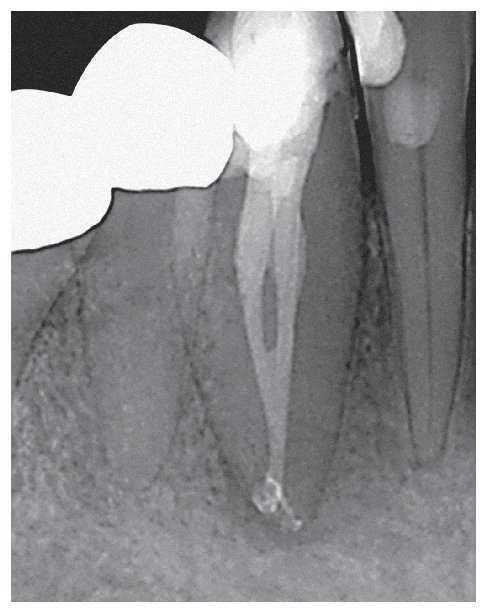

Figura 1d. Situación clínica en el momento de la adaptación del cono maestro para la compactación vertical en caliente.

Figura 1e. Radiografía de control después de la obturación termoplástica. Se logró una obturación homogénea y completa de este sistema de conductos radiculares complejo.